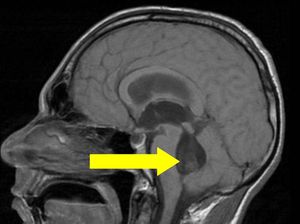

The Bruns syndrome is an unusual phenomenon, characterized by attacks of sudden and severe headache, vomiting and vertigo, triggered by abrupt movement of the head. The presumptive cause of the Bruns syndrome is a mobile deformable intraventricular lesion leading to an episodic obstructive hydrocephalus resulted from an intermittent or positional CSF obstruction with elevation of intracranial pressure due to a ball-valve mechanism. Although the old neurological literature recognized tumors as well as neurocysticercosis as causes of the Bruns syndrome, during the last 60 years only intraventricular neurocysticercosis was reported to cause this symptom-complex. Relapsing attacks of headache, vertigo, nausea, vomiting, and ataxia provoked by head rotation corresponding to the classical Bruns syndrome.